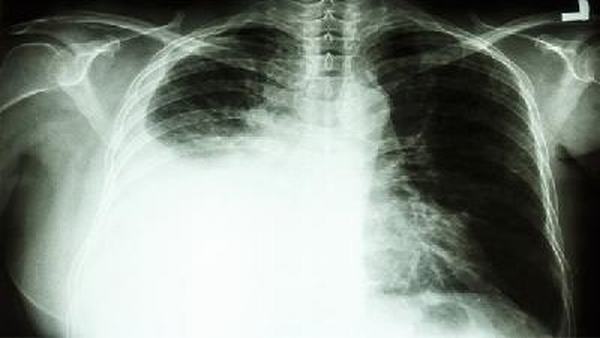

首先,我们需要了解气胸的分类。气胸可以分为原发性和继发性两种。原发性气胸多为年轻男性出现,与患者个体发育异常有关,通常不需要手术干预,绝大多数患者经过适当休息和观察会自行康复。继发性气胸则是由其他疾病,如肺部疾病或外伤引起的,需要根据具体情况进行治疗。所以,在回答气胸患者是否适合运动的问题时,应根据具体情况进行综合分析和判断。